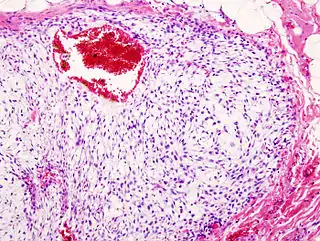

![]() Imagen de un condrosarcoma. Tinción H&E. | ||

El condrosarcoma es un tumor maligno mixto que presenta células formadoras de tejido cartilaginoso y elementos embrionarios. Está formado por cartílago hialino y mixoide maligno. El comportamiento de este tumor es variable, existen formas de crecimiento lento con pocas posibilidades de metástasis y otras formas agresivas con gran probabilidad de diseminarse y hacer metástasis. Más de 90 % son de grado histológico bajo o intermedio, con crecimiento lento y un bajo potencial de metástasis. Solo del 5 al 10 % de los condrosarcomas son de grado 3, los cuales sí tienen una alta incidencia de metástasis.